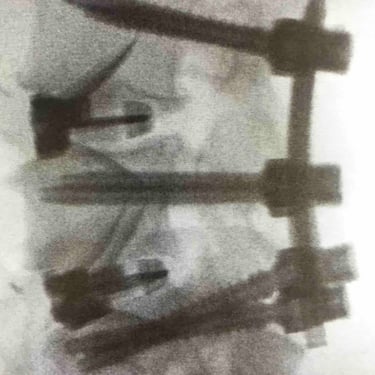

Spinale Neurochirurgie

Wirbelsäulenchirurgie

Wirbelgleiten

Traumatische Verletzungen der Wirbelsäule